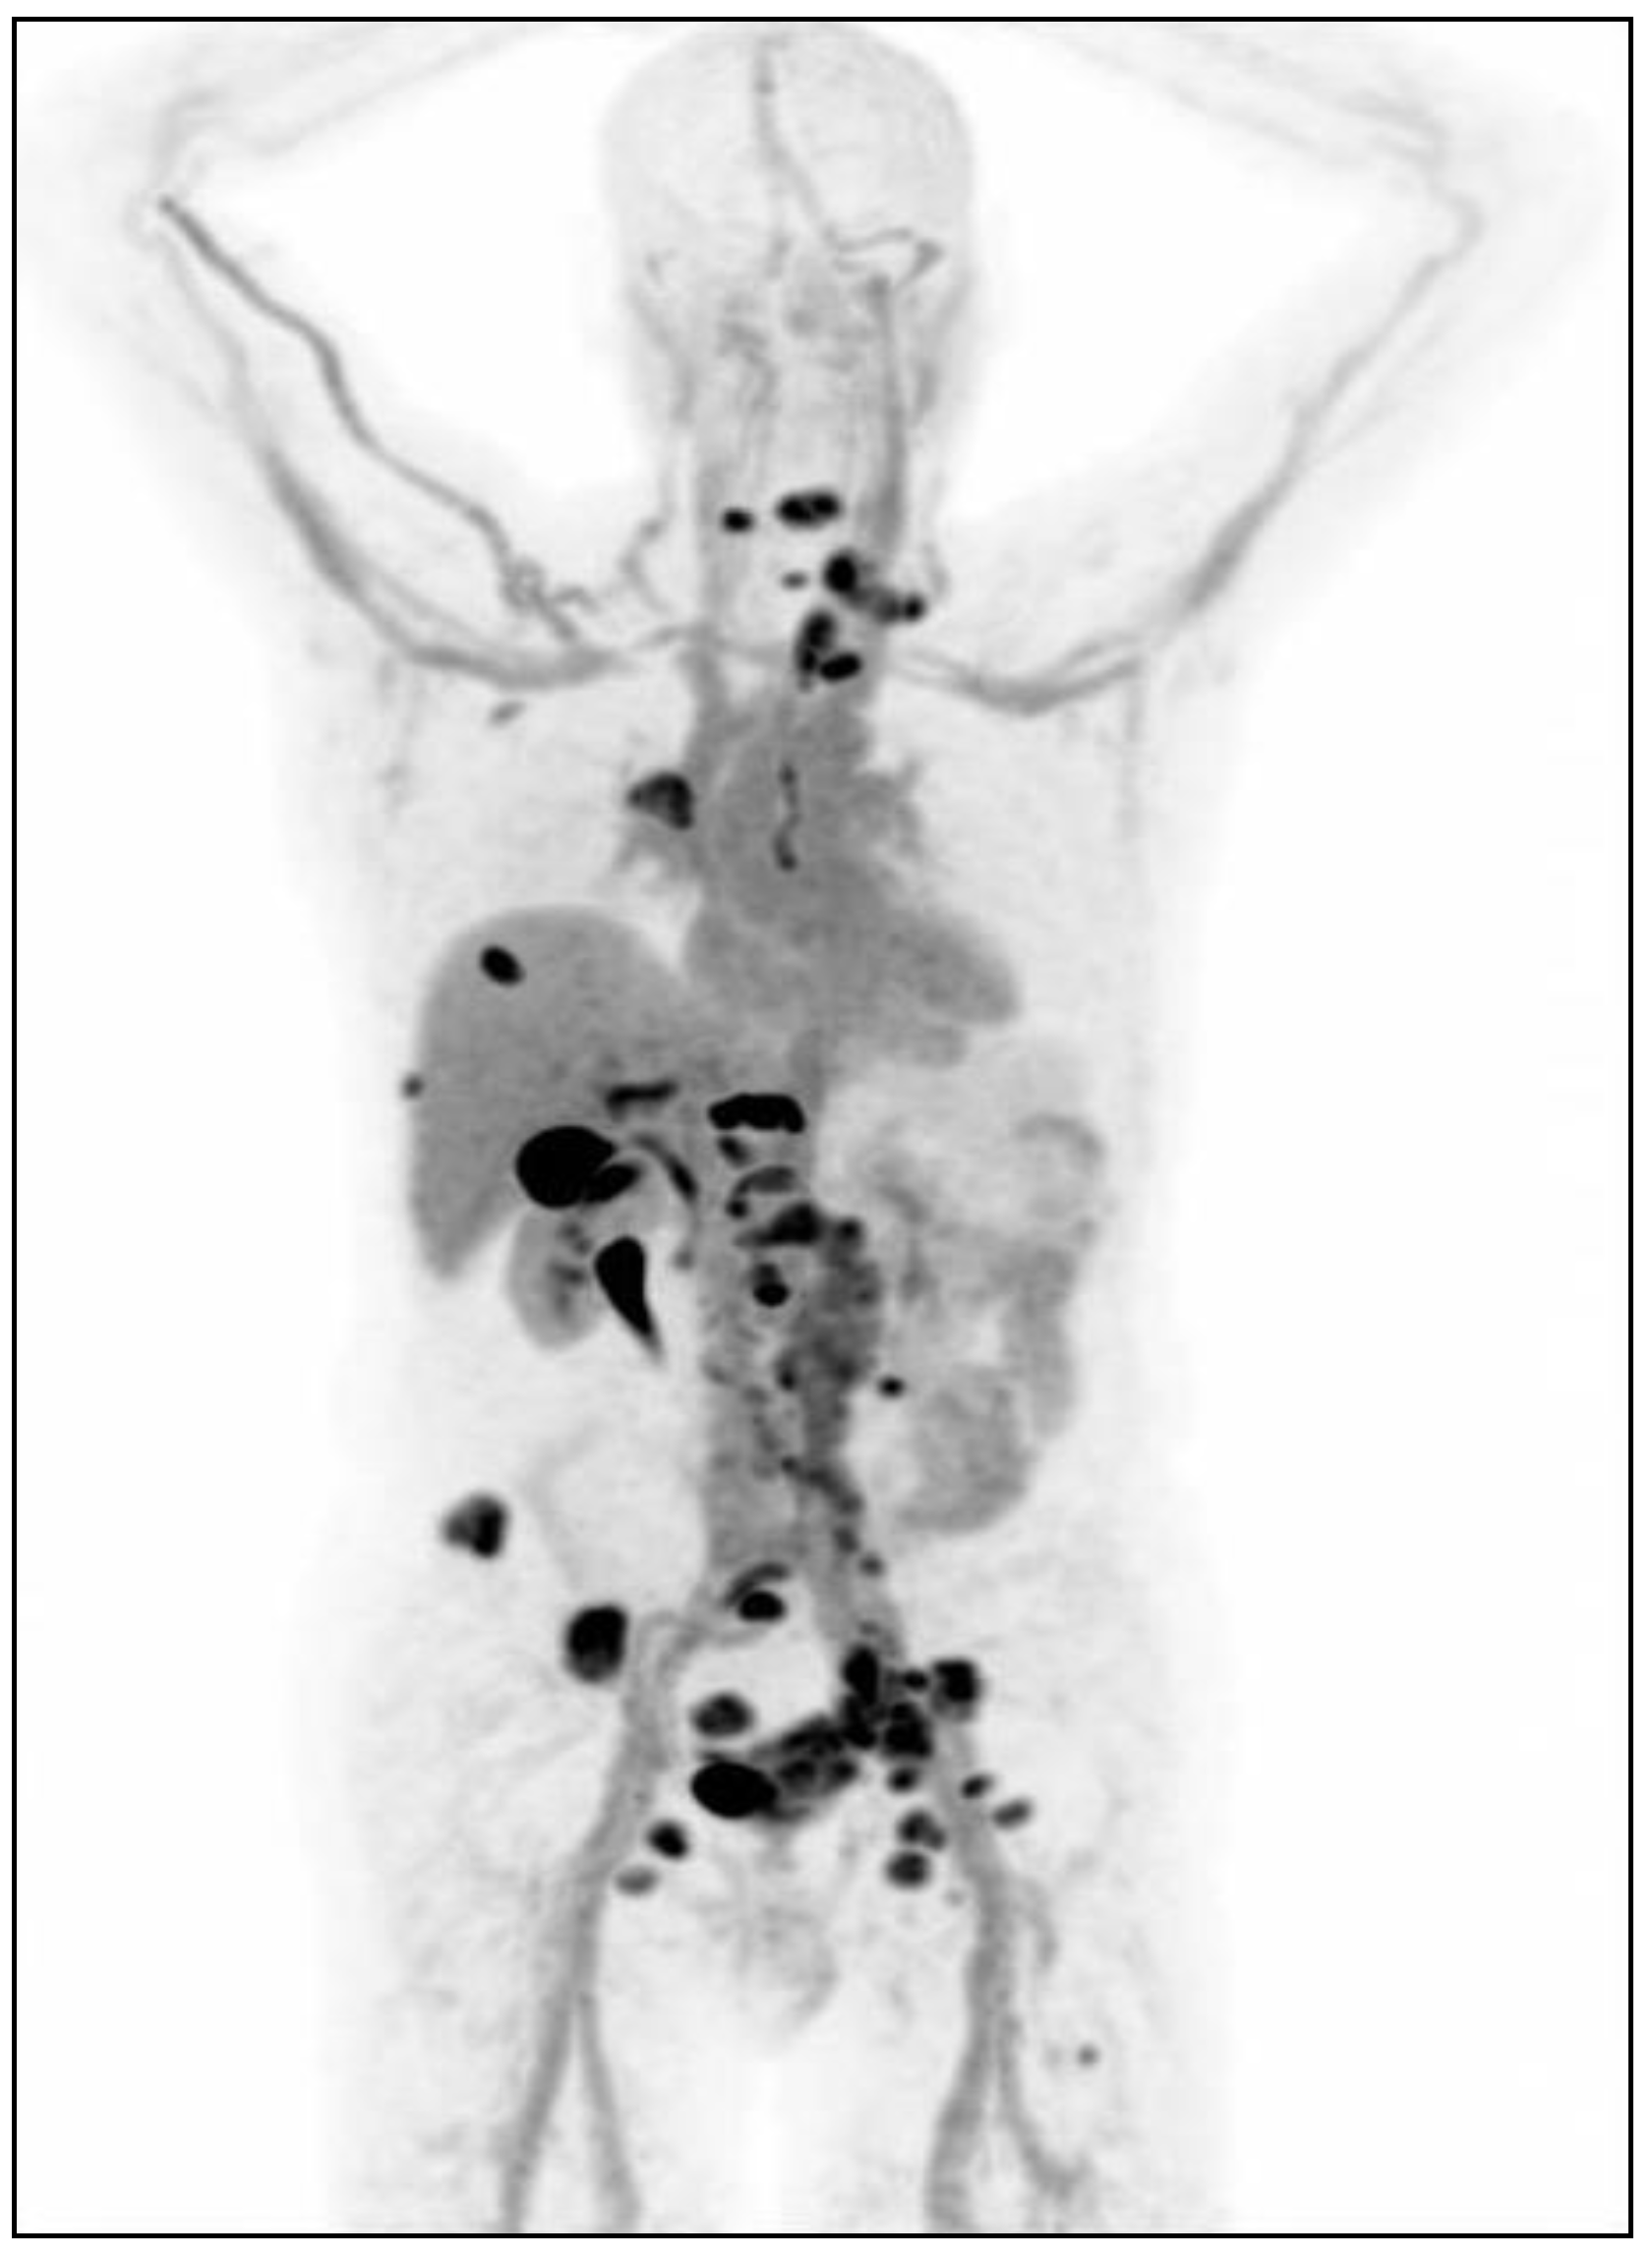

- Chan, D.L.H.; Pavlakis, N.; Schembri, G.P.; Bernard, E.J.; Hsiao, E.; Hayes, A.; Barnes, T.; Diakos, C.; Khasraw, M.; Samra, J.; et al. Dual Somatostatin Receptor/FDG PET/CT Imaging in Metastatic Neuroendocrine Tumours: Proposal for a Novel Grading Scheme with Prognostic Significance. Theranostics 2017, 7, 1149–1158. [Google Scholar] [CrossRef]

- Abdulrezzak, U.; Kurt, Y.K.; Kula, M.; Tutus, A. Combined imaging with 68Ga-DOTA-TATE and 18F-FDG PET/CT on the basis of volumetric parameters in neuroendocrine tumors. Nucl. Med. Commun. 2016, 37, 874–881. [Google Scholar] [CrossRef]